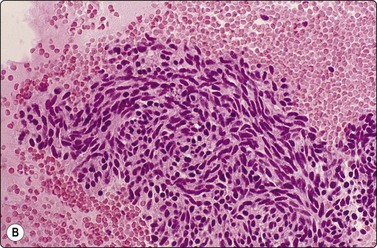

Granulomatous inflammation (Figs 8.5-8.7)98-103,170-176

image

Fig. 8.5 Granulomas

Clustered epithelioid histiocytes and lymphocytes (H&E, HP).

Criteria for diagnosis

Epithelioid histiocytes in cohesive clusters,

Few nonpigmented multinucleate histiocytes,

Granular, calcific, mucoid or acute inflammatory debris (corresponding to caseous necrosis in TB),

Lymphocytes.

Epithelioid histiocytes are fairly cohesive and form granulomas which are often aspirated intact (Fig. 8.5). Epithelioid cells have an elongated or bean-shaped nucleus and abundant cytoplasm which is rather pale and indistinct both in Pap- and H & E-stained specimens (Fig. 8.5). The cytoplasmic density is higher in MGG-stained material. Multinucleated histiocytes can be seen but are usually sparse. They are mainly free of intracytoplasmic pigment or birefringent material, unlike the multinucleated histiocytes seen in non-specific reactions in pulmonary tissue. Caseous necrosis has a variable appearance. There may be an amorphous to granular background with little cell outline visible, but sometimes outlines of necrotic cells may be prominent (Fig. 8.6) and often the appearances are merely of nondescript debris, histiocytes and neutrophils. Dahlgren cites granular calcific material as a common accompaniment.98 Lymphocytes may be plentiful in granulomatous inflammation.